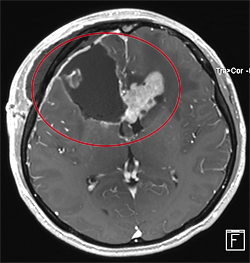

悪性腫瘍の手術前

手術後

放射線・化学療法後